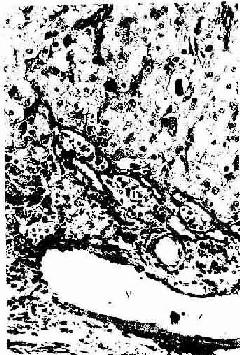

卵巢表面覆盖一层单层扁平或立方的表面上皮,上皮下方为薄层致密结缔组织构成的白膜。卵巢的外周部分称皮质,中央为髓质。皮质较厚,含有不同发育阶段的卵泡以及黄体和退变的闭锁卵泡等,卵泡间的结缔组织富有网状纤维和梭形基质细胞。髓质由疏松结缔组织构成,与皮质无明显分界,含有许多血管和淋巴管等。近卵巢门处有少量平滑肌束及门细胞(图17-1)。

图17-1 卵巢

4.成熟卵泡 成熟卵泡(mature follicle)是卵泡发育的最后阶段。卵泡体积很大,直径可达20mm,并向卵巢表面突出(图17-1,17-5)。成熟卵泡的卵泡腔很大,颗粒层甚薄,颗粒细胞也不再增殖。此时的初级卵母细胞又恢复成熟分裂,在排卵前36~48小时完成第一次成熟分裂。产生1个次级卵母细胞(secondary oocyte)和1个很小的第一极体(first polar body)。第一极体位于次级卵母细胞和透明带之间的卵周间隙(perivitelline space)内。次级卵母细胞随即进入第二次成熟分裂,停止于分裂中期。人每个月经周期,可有若干个原始卵泡生长发育,通常只有1个卵泡发育成熟并排卵。

图17-5 猫卵巢内的近成熟卵泡 HE×160

(四)卵泡闭锁与间质腺

卵巢的绝大部分卵泡不能发育成熟,它们在卵泡发育的各阶段逐渐退化,退化的卵泡称为闭锁卵泡(atresic follicle)(图17-1,17-5)。卵泡闭锁时形态结构的变化与卵母的大小相关。原始卵泡退化时,卵泡细胞首先出现核固缩,细胞形态不规则。卵泡细胞变小且分散,两种细胞随后均自溶消失。初级卵泡和早期次级卵泡的退化与原始卵泡相似,但退化的卵泡内可见残留的透明带,卵泡腔内常见中性粒细胞和巨噬细胞。晚期次级卵泡的闭锁变化较特殊,卵泡塌陷,卵泡膜的血管和结缔组织伸入颗粒层及卵丘,膜细胞一度增大,形成多边形上皮样细胞,胞质中充满脂滴,形似黄体细胞,并被结缔组织和血管分隔成分散的细胞团索,称为间质腺(interstitial gland)。成人卵巢间质腺细胞数量少,且散在分布于基质中;猫及啮齿动物卵巢的间质腺较多,有分泌雌激素的功能。